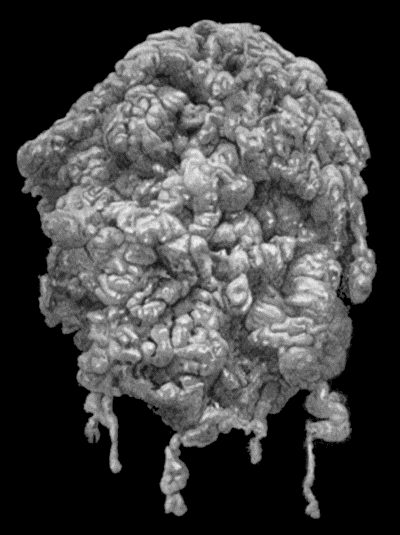

| 30. | Colony of Actinomyces | 126 |

| 31. | Actinomycosis of Maxilla | 128 |